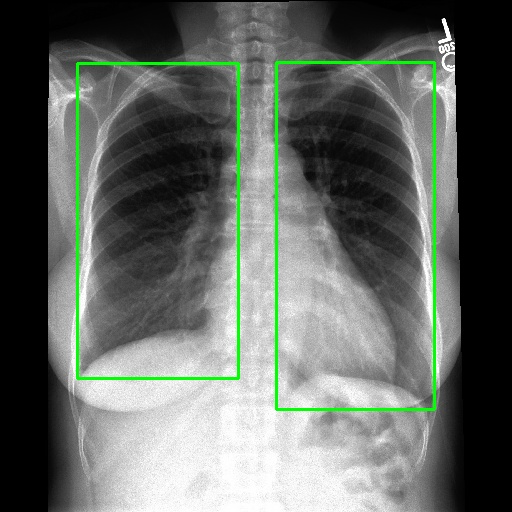

We employ appropriate strategies to locate ROIs for images paired with different annotations. For datasets that already include localization annotations, such as segmentation masks or bounding boxes, we derive the ROIs from these paired annotations. Specifically, bounding boxes are directly used as the ROIs, while segmentation masks are converted to ROIs by creating the smallest bounding box that covers the mask. When such localization annotations are not available, we apply corresponding pretrained expert models to generate ROIs. More details about the selection of expert models are provided in Appendix D. Examples of generated ROIs from various modalities using corresponding models are demonstrated in Figure 6. For modalities such as X-ray and MRI scans viewed from the z-axis, our ROI localization employs a coordinate system relative to the human body, resulting in a left-right reversal in the image representation.

Refer to caption

(a) Example of locating ROI via SAT (Zhao et al., 2023).

(b) Example of locating ROI via BA-Transformer (Wang et al., 2021).

(c) Example of locating ROI via Chexmask (Gaggion et al., 2022).

Figure 6: Example of ROIs and their corresponding textual descriptions.